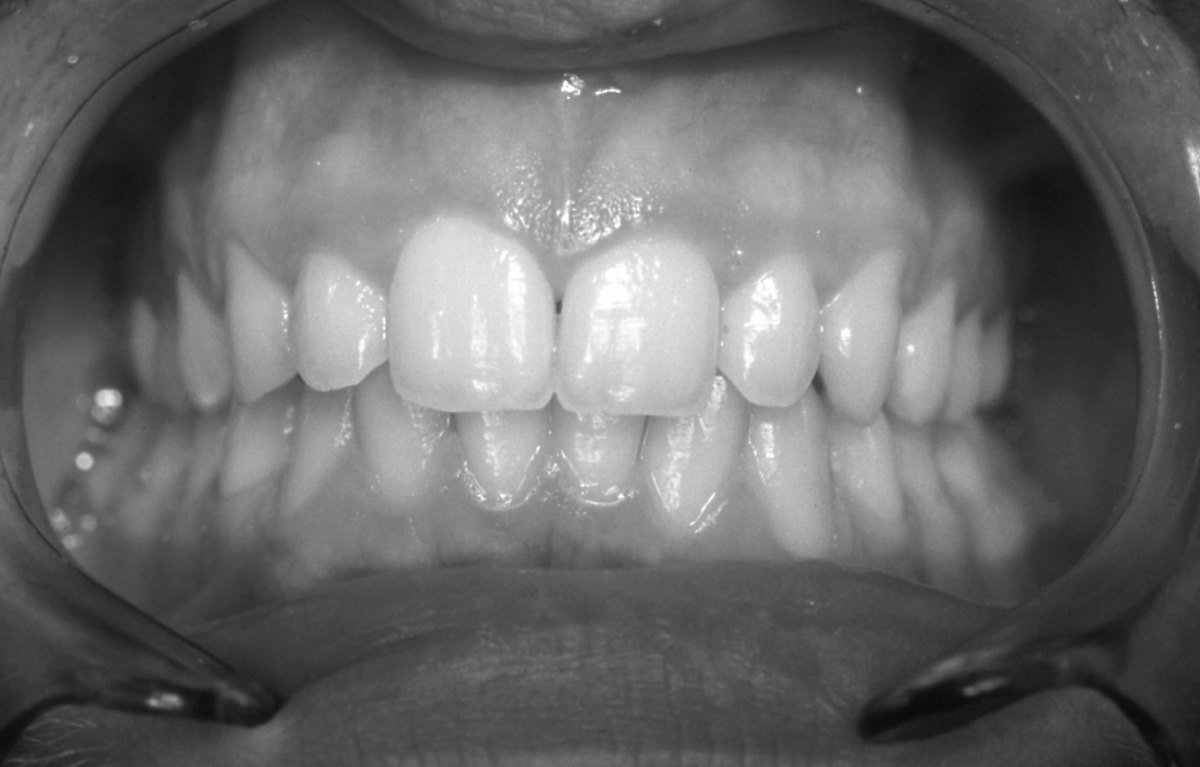

От баланса на нашите зъби зависят психичното здраве и емоционалният ни комфорт (интервю)